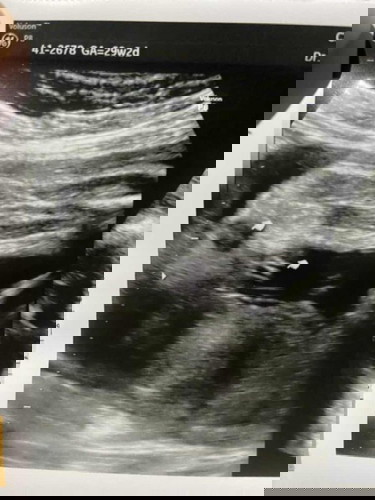

แม่ๆช่วยดูหน่อยค่า น้องเป็นผู้หญิงหรือว่าผู้ชาย ท้องแรกค่า ขอบคุนล้วงหน้าค่าา

ดูจากภาพนี้แล้วดูไม่ค่อยออก แต่น่าจะ ญ ไหมคะ มีภาพอื่นที่เห็นขา2ข้างชัดไหมคะ

หญิงค่ะ เป็นกลีบมาเลย🥰🥰🥰✌️

หมอบอก ผ.ญ แต่แม่ไม่ค่อยมั่นใจ เห็นเปนแหลมๆกลัวจะเป็นจู๋😃

ไม่แน่ใจน่าจะเป็น ญ ไหมคะ

น่าจะเป็นผู้หญิงนะแม่

น่าจะผู้หญิงนะคะ

ผู้หญิงค่ะ

น่าจะญ